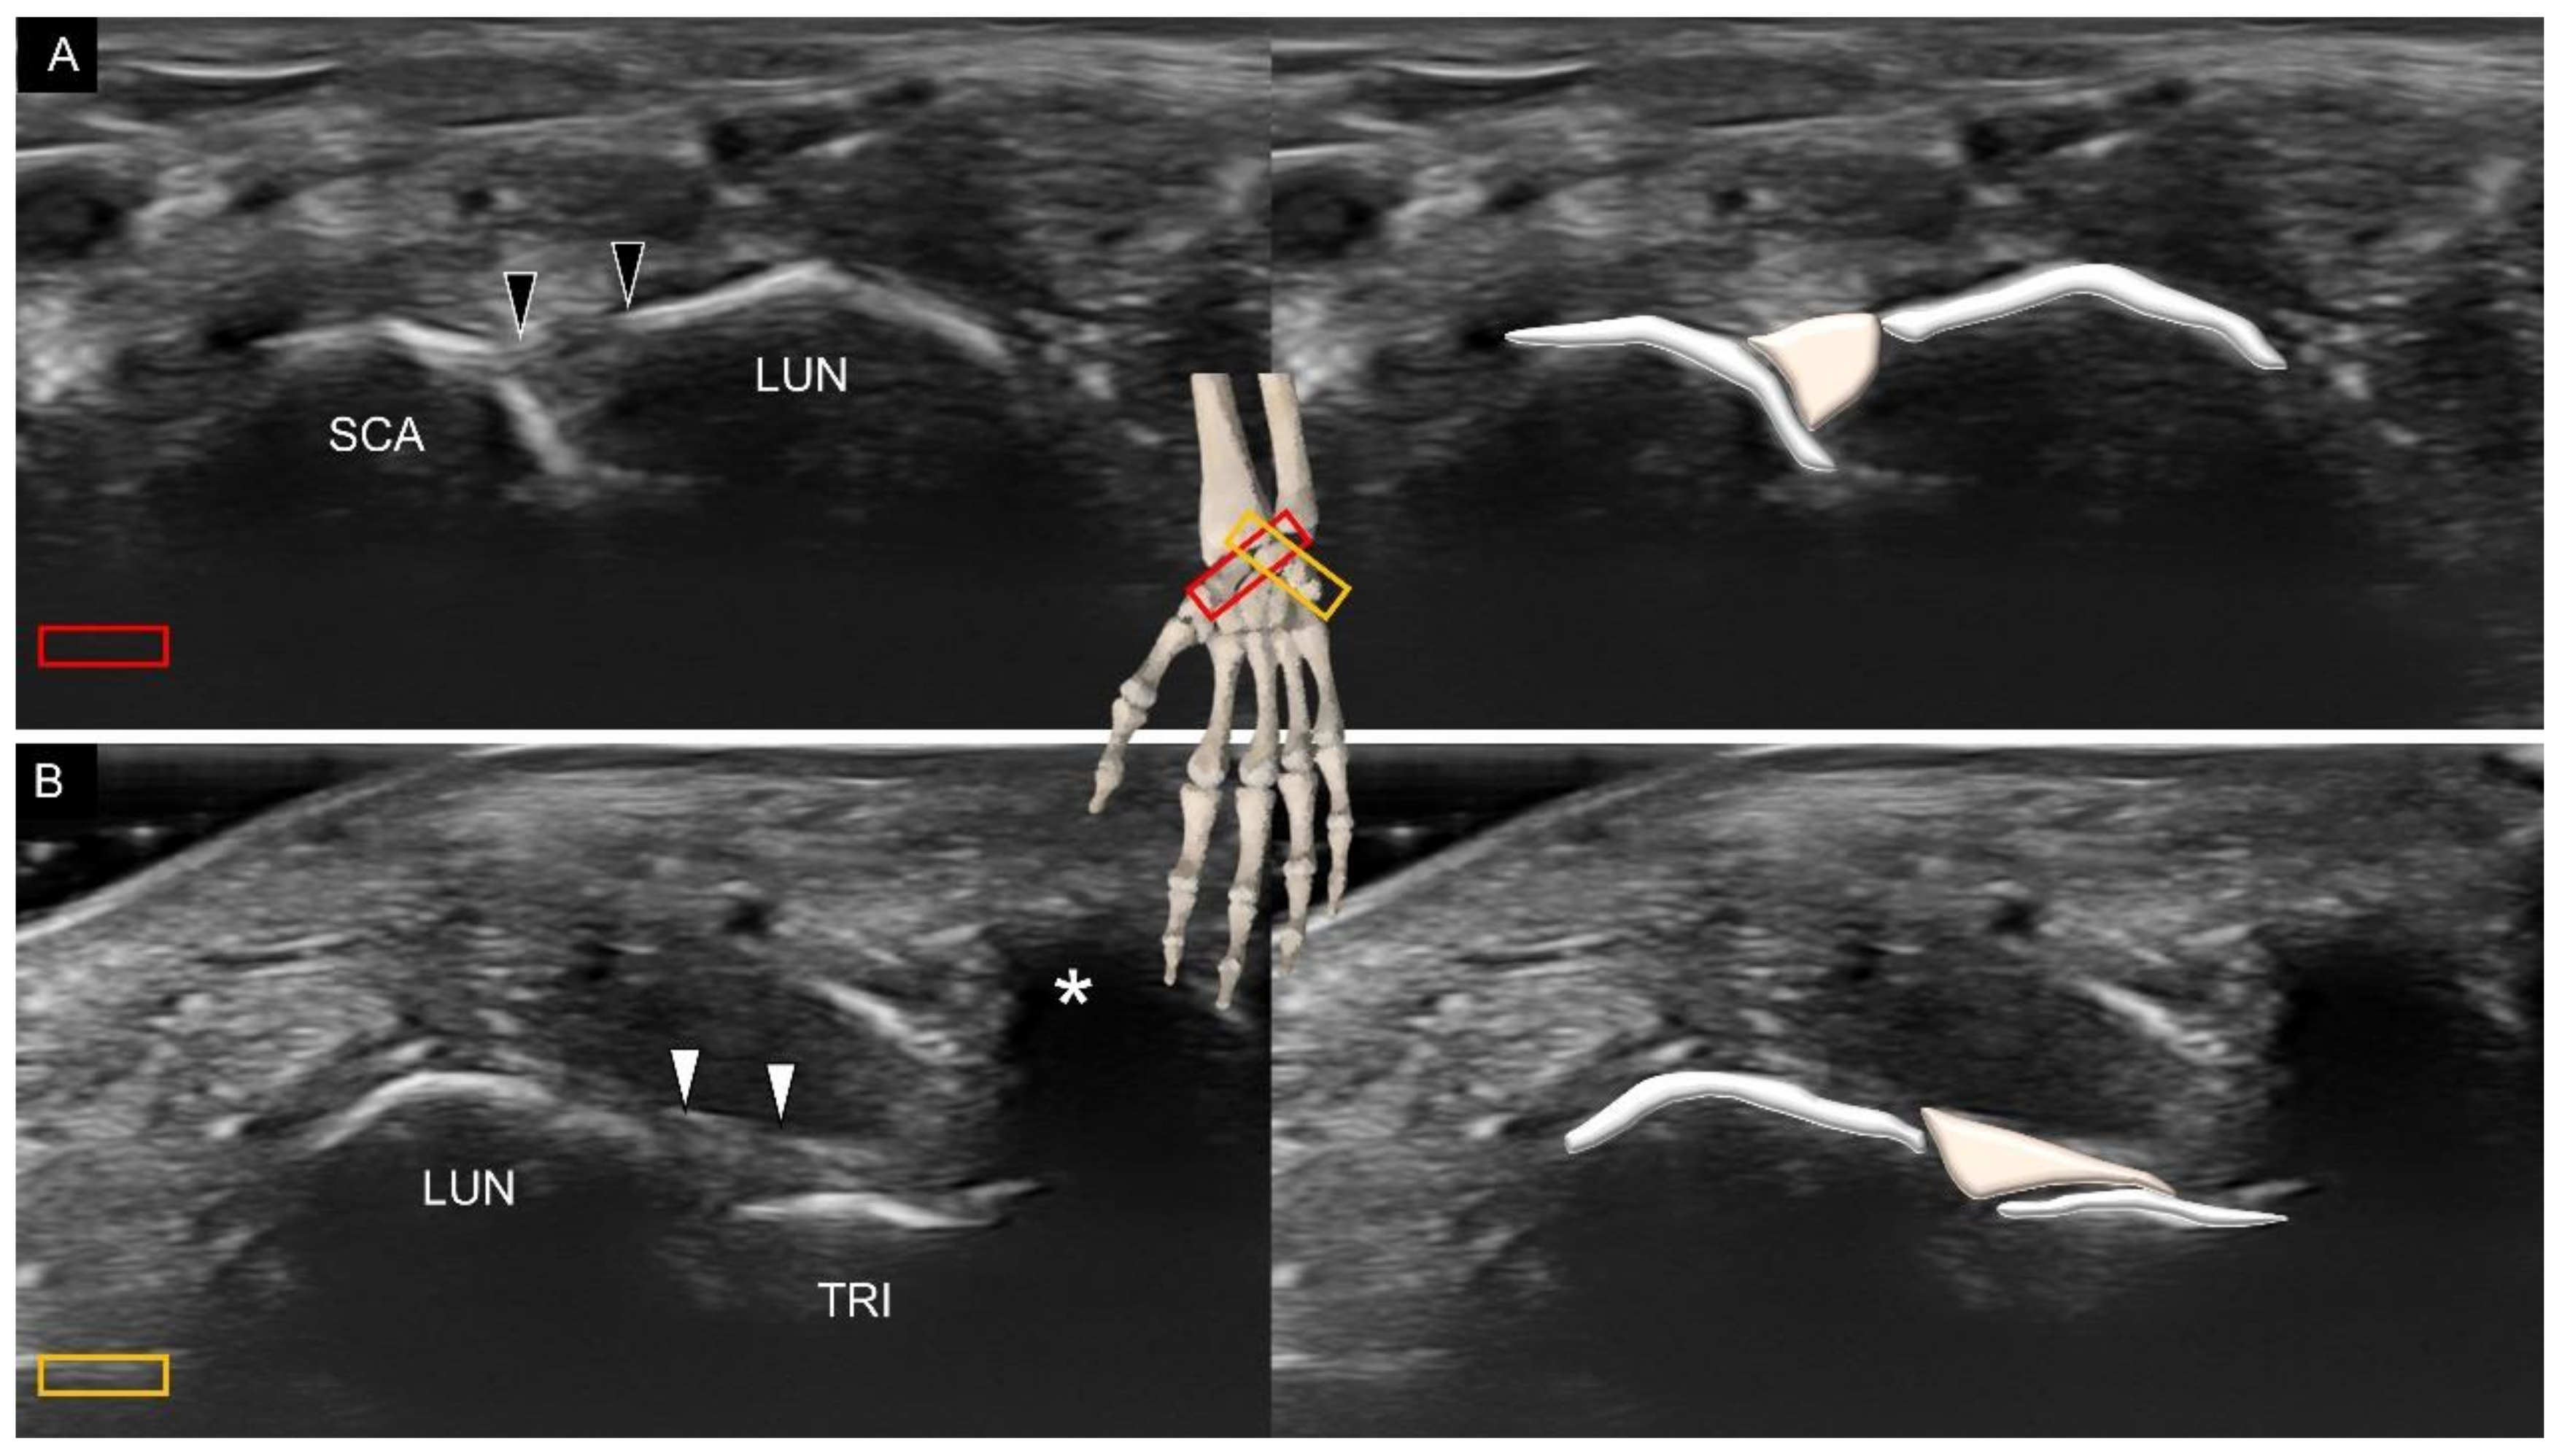

4. Sonoanatomy of Volar Intrinsic Carpal Ligaments

6. Sonoanatomy of Dorsal Intrinsic Carpal Ligaments